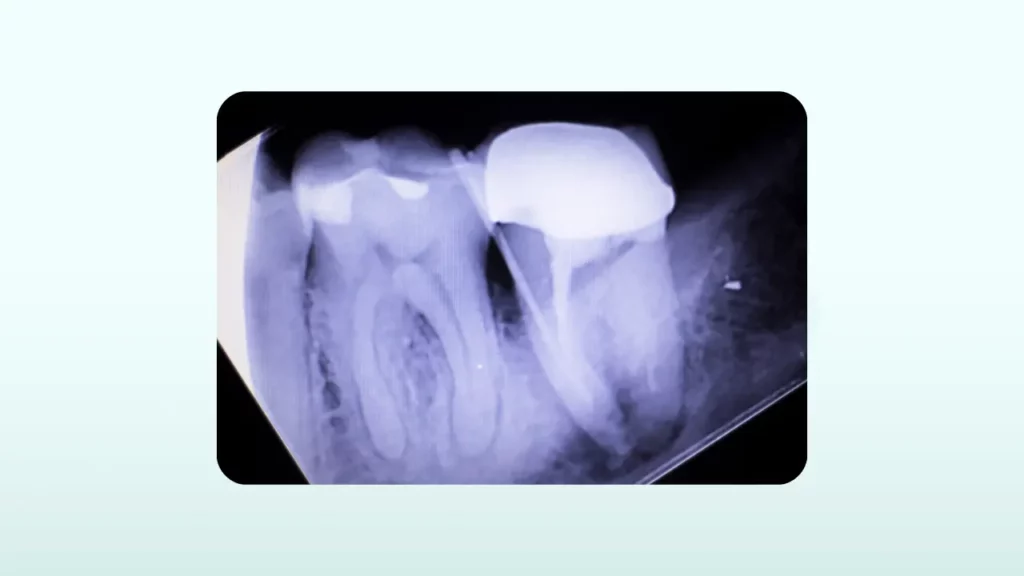

بدترین و نادرترین سناریو، شکستگی عمودی ریشه است

این دلیل، نادرترین اما جدی ترین علت درد دندان روکش شده است. درد در این حالت معمولاً مبهم و مداوم است و هنگام جویدن بدتر می شود. ممکن است یک جوش چرکی روی لثه کنار دندان هم وجود داشته باشد که گاهی فعال می شود. تشخیص این مشکل معمولاً سخت است و نیاز به عکس های دقیق دارد.

این اتفاق بیشتر در دندان هایی که عصب کشی شده اند و با پین های فلزی بلند تقویت شده اند، رخ می دهد و فشار مداوم جویدن می تواند باعث ایجاد یک ترک عمودی در طول ریشه شود. متأسفانه، شکستگی عمودی ریشه تقریباً همیشه غیرقابل درمان است و تنها راه حل، کشیدن دندان و جایگزینی آن با ایمپلنت یا بریج است.